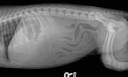

RadioQuiz 15 – Nouveau chiot, nouveau problème

19 février 2013